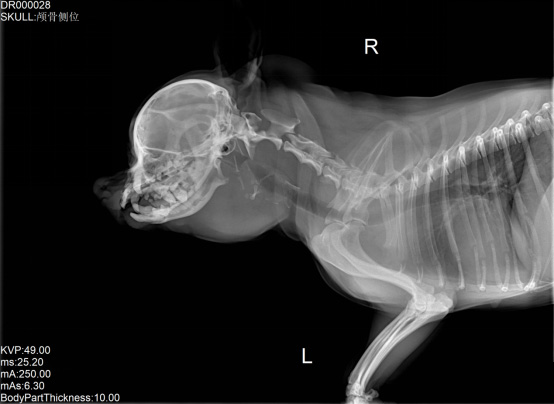

寵物DR是專業(yè)用于寵物X光拍攝的數(shù)字化X射線檢查,輔助寵物醫(yī)生進(jìn)行及時(shí)精確的診療。寵物DR主要包括五大主要部件,數(shù)字X光探測器,高壓發(fā)生器,球管,機(jī)架,寵物專用的DR工作站軟件。寵物DR由于采用數(shù)字技術(shù),自動(dòng)成像處理,模擬X線圖像向數(shù)字化X線圖像的轉(zhuǎn)變。寵物DR與傳統(tǒng)模擬X光機(jī)相比有什么優(yōu)勢呢?采集時(shí)間10毫秒以下,成像時(shí)間僅為3秒,較高的空間分辨力和低噪聲率,提高了病灶的檢出率,避免漏診誤診等問題。減少X線對(duì)人體照射的不良影響寵物DR照片是您最佳的選擇。提高寵物醫(yī)生工作效率,總而言之,選擇寵物DR是寵物醫(yī)院的最佳選擇。寵物醫(yī)學(xué)影像學(xué)實(shí)現(xiàn)全數(shù)字化和無膠片化升級(jí)發(fā)展提高技術(shù)水平。